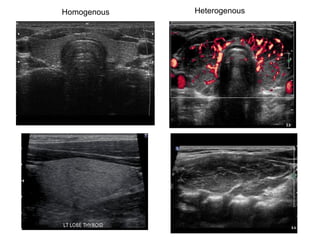

Thyroid gland

Homogenous Heterogenous

Multinodular goiter Coarse calcification

Suspicious signs of malignancy by US

• Hypoechoic nodule

• Irregular/ill-defined

margins

• Microcalcifications

without shadowing

• Intranodular vascular

flow on Doppler

carotid

trachea

Nodule

irregular margin